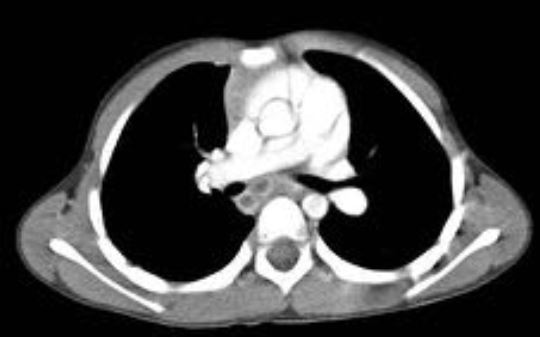

2.- Describir las anomalías radiológicas detectadas en la TC torácica del grupo de niños afectos de enfermedad tuberculosa durante el período de estudio, especialmente las características morfológicas de las adenopatías.

3.- Comparar los hallazgos detectados en la TC torácica del grupo de niños asintomáticos, con prueba de tuberculina (PT) positiva y radiografía de tórax normal, con los encontrados en el grupo de niños sintomáticos, diagnosticados de enfermedad tuberculosa activa.